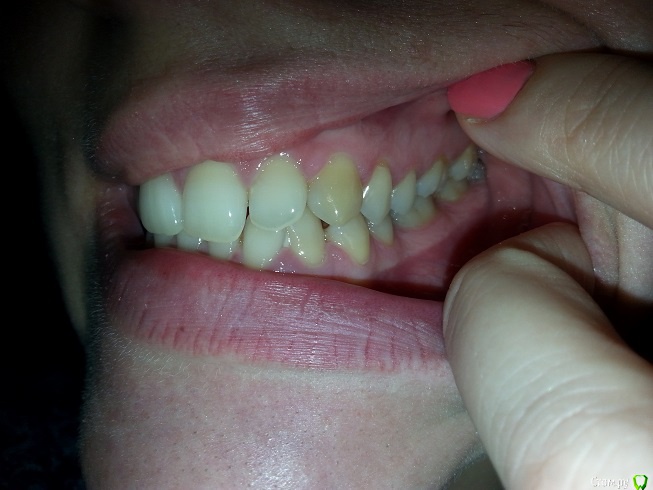

zimazima Опубликовано 20 ноября, 2015 Поделиться Опубликовано 20 ноября, 2015 Добрый вечер!Опытные ортодонты, скажите, пожалуйста, будет ли необходимо в моем случае удалять нижние 4ки? Какова вероятность того что НЧ выйдет вперед после ношения брекетов? предыстория: в 17 лет носила брекеты на ВЧ, т.к. слева клык рос поверх ряда удалили 4ку и поставили на ее место клык...при этом ВЧ потеряла симметрию((и кажется что проявилось это спустя годы (сейчас мне 30). и теперь за счет того что НЧ не ровнялась зубы начали разворачиваться опять... вопросы:- какова вероятность того что удаление нижних 4к не потребуется при лечении?(ортодонт говорит что можно поносить пол года и посмотреть в процессе, имеет ли это смысл? или лучше не терять время, может все очевидно?...)- можно ли оставлять 8ки?- реально ли вернуть центр ВЧ на место если удалить 4ку слева?- при удалении нижних и верхних 4к как сильно сузится лицо и подбородок станет ли еще более выпирающим? (лицо у меня и без того узкое и длинное, достаточно большой нос картошкой и выступающий подбородок) не станет ли хуже?- не будет ли после лечения других проблем с искривлением лица (оно у меня сейчас не симметричное - глаза на разном уровне))), на фото вижу особенно это(( в общем в жизни не так вроде бы все и плохо выглядит - на фото просто кошмар - сама посмотрела и уже готова на все.волнуюсь не будет ли хуже в моем случае? очень благодарна за любые ответы - советы - комментарии! спасибо!выложу доп фото по запросу любые нужныеЗлобина А.В. Заключение.pdf Ссылка на комментарий

m.d.n Опубликовано 21 ноября, 2015 Поделиться Опубликовано 21 ноября, 2015 эммм ну можно тут по разному работать. внизу кроме 8 ничего неудалял бы вообще. если побыстрее то слева 4. если не торопитесь то все 8 удалить открыть место под удаленный премоляр вернуть центры и имплант вместо ранее удаленного .как то так Ссылка на комментарий